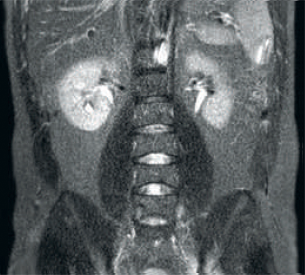

Resultado: imágenes ruidosas que usan parámetros de exploración idénticos

Mayor consistencia y mejor calidad de imagen La tecnología de recepción de RF dStream digitaliza la señal del RM directamente en la bobina de radiofrecuencia, lo que resulta en un aumento de hasta un 40 % más de la SNR* en todo el volumen de la imagen. Flujo de trabajo simplificado y rendimiento mejorado La bobina posterior integrada en la mesa elimina el manejo de la bobina en el 60 % de los exámenes. Las ligeras bobinas anteriores conformadas y las conexiones de bobina de un solo cable y de una sola mano contribuyen a la facilidad operativa.